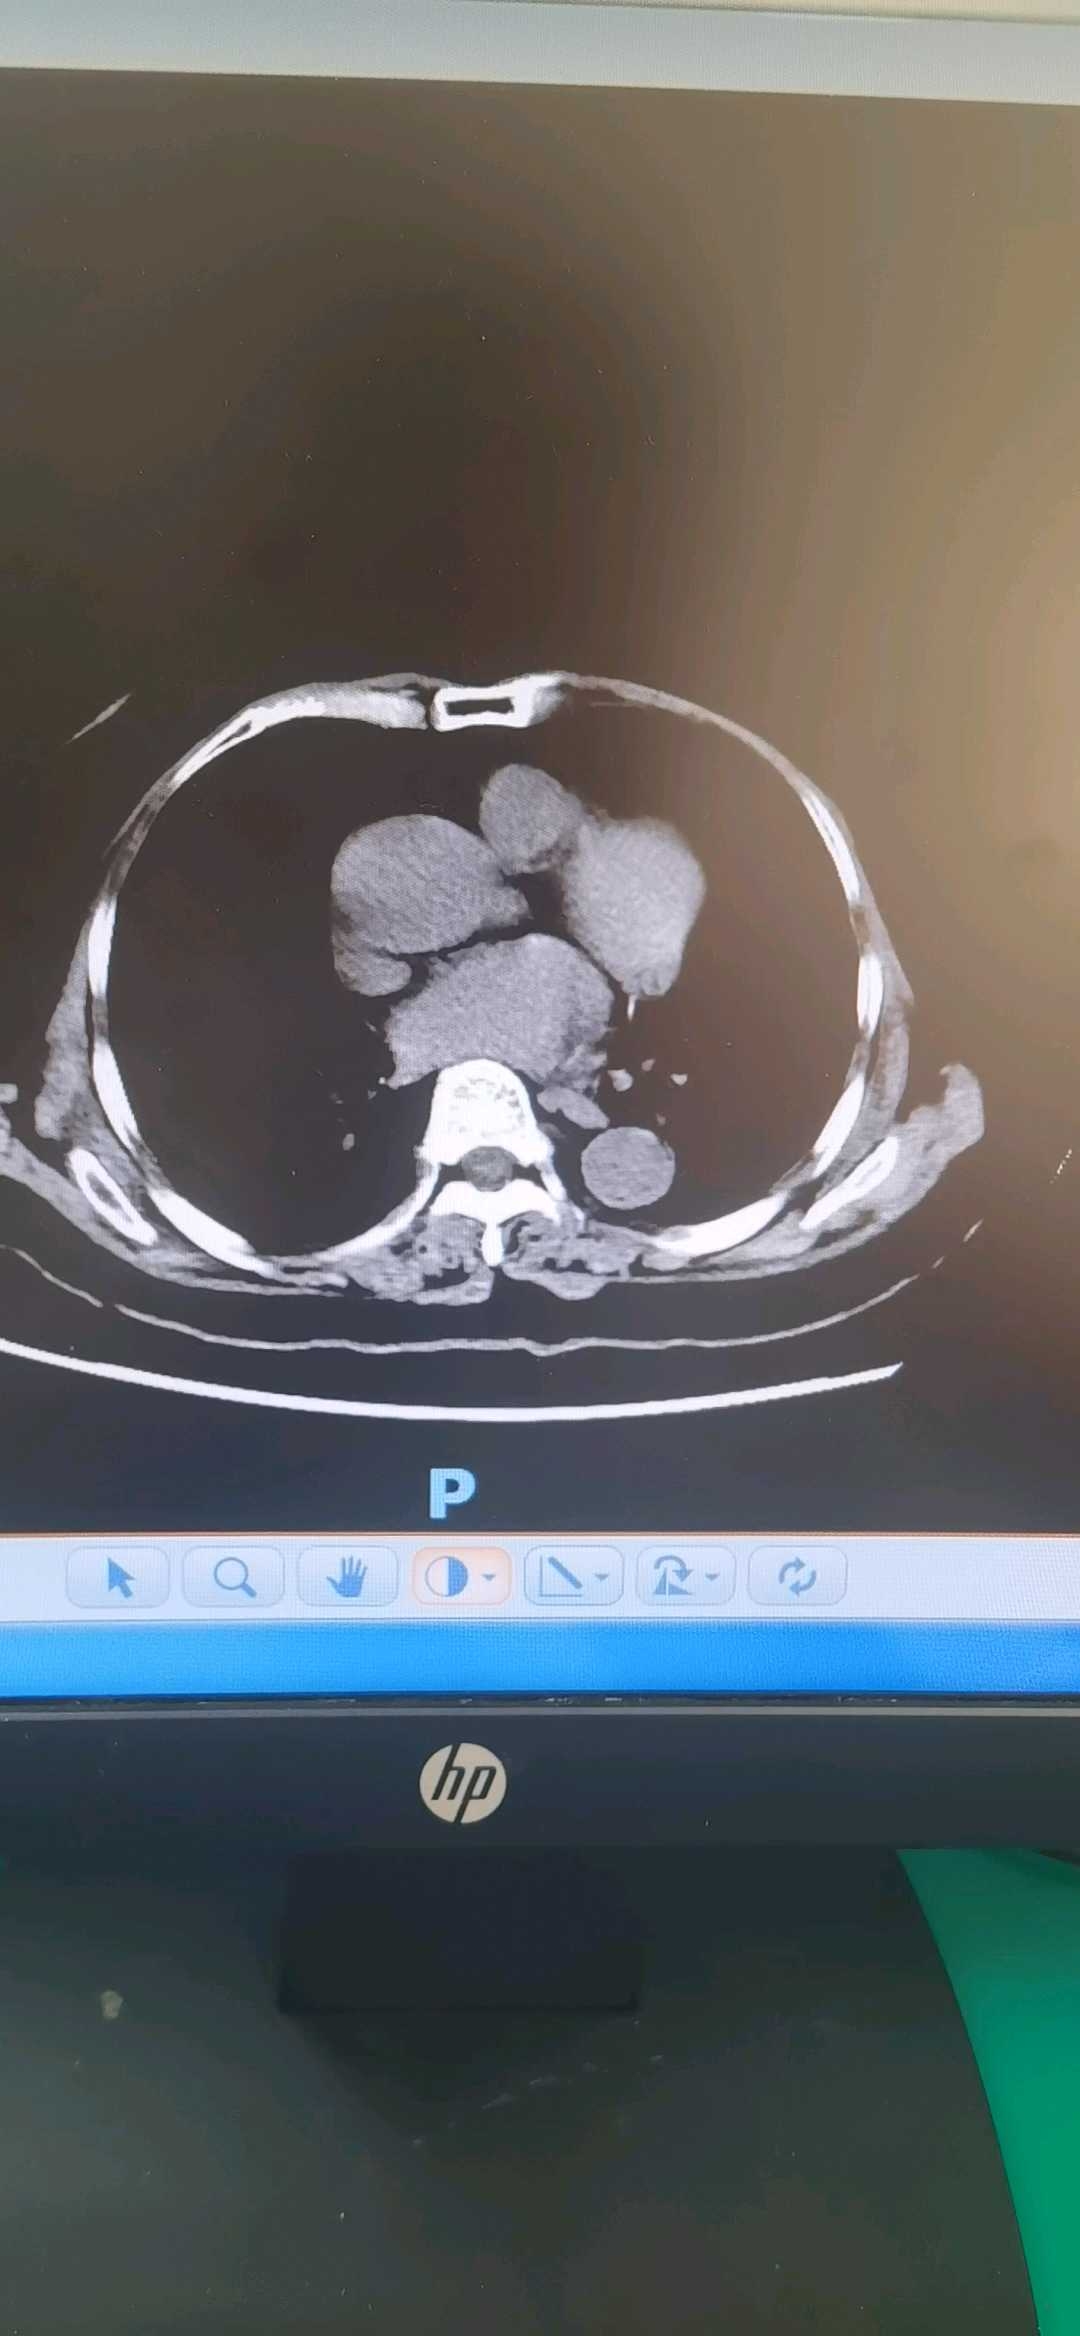

67岁女性,ERCP胆管支架置入术后3个月来诊拔除支架。术前CT如下

CT能否看出胃的走向异常?侧视镜检查时如何避免胃腔成襻